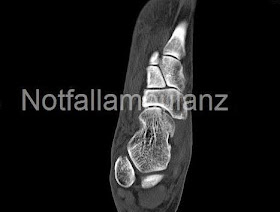

Als erstes schloss sich das CT an:

Hier imponieren Veränderungen am Caput tali, die am ehesten einer sklerosierten avaskulären Nekrose ähneln, also älteren datums sind und begünstigend für die Luxation sein konnten. Eine akute frische Fraktur möchte man nicht vermuten.